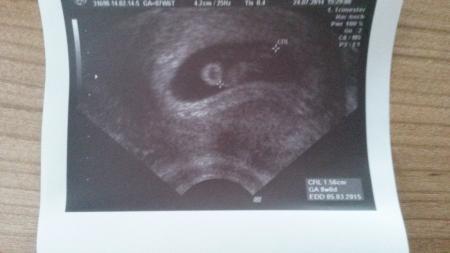

Danke ist lieb - kuck mal unser kleiner krümel :)

Bild zu